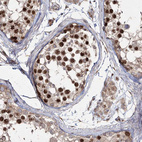

Immunohistochemistry analysis in human testis and pancreas tissues using HPA034521 antibody. Corresponding PRC1 RNA-seq data are presented for the same tissues.